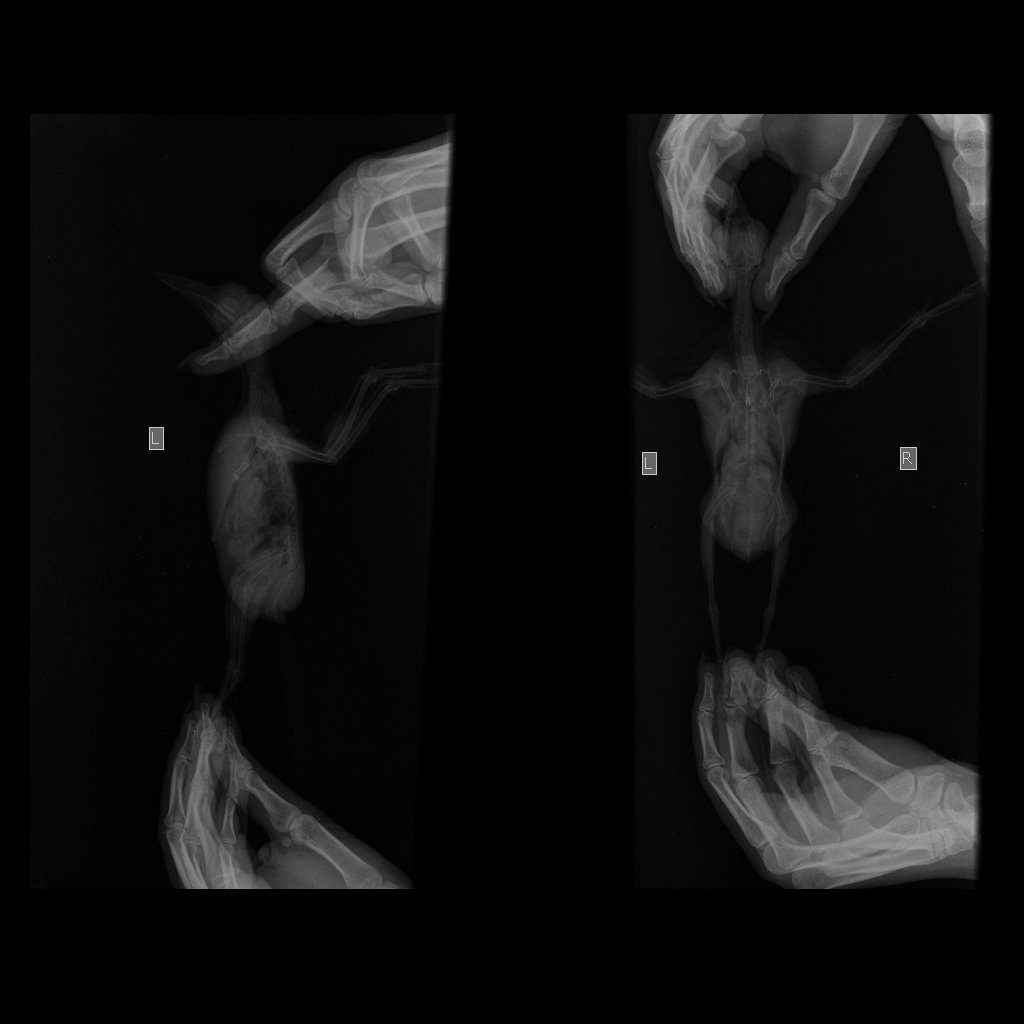

Доброй ночи. Подобрала иволгу на улице. Видела как она падала с дерева. Птица на лапы не становится, но раскрывает их и пытается схватиться. Летает хорошо. Пытается защищаться, щелкает клювом и щиплется. Живёт в большой картонной коробке. Кормлю насильно сверчками и мраморными тараканами. Пьет воду из шприца. В туалет ходит только когда вытаскиваем из коробки. Чем можно помочь птице? Вес 91г.

IMG-77e39bf754a9d0cb8e7a9897144a605c-V.jpg

IMG_20200912_134326.jpg

IMG_20200908_170127.jpg